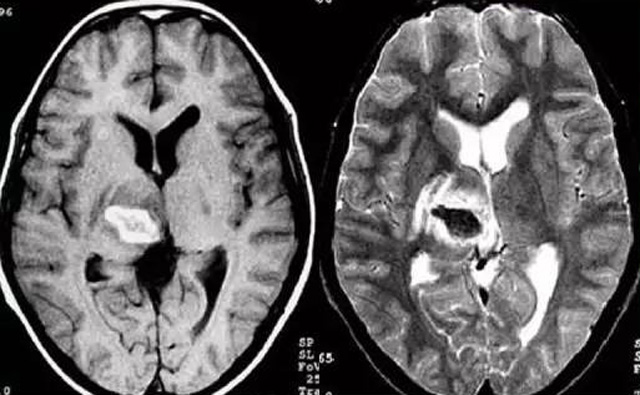

經(jīng)顱多普勒超聲(TCD)磁共振MRI檢查腦出血診斷的作用是什么?

發(fā)現(xiàn)病人出血腦梗相關(guān)癥狀時候第一時間就醫(yī),需要攜帶以往的影像檢查資料。向醫(yī)生提供相關(guān)的病史基本資料。做影像檢查時候需要全身不攜帶金屬物品。檢查時候身體保持不動,不然偽影對檢查結(jié)果有干擾。磁共振MRI發(fā)現(xiàn)缺血性卒中后,幫助進一步查找病因。由于CT上小腦跟腦干顱骨影響,容易導(dǎo)致漏診。MRI檢查可以對CT檢查不足的補充。短暫的腦缺血TIA也需要進行影像檢查。短暫性缺血一般10幾分鐘后好轉(zhuǎn)。檢查目的可以確定TIA的病因。降低腦梗死的發(fā)生率。磁共振有助于排出TIA表現(xiàn)的顱內(nèi)病變,有診斷及時治療的價值。磁共振MRI檢查時間比較長,不太適合急診病人。但是可以發(fā)現(xiàn)腦干小腦的出血問題。因為急性腦梗死的早期和急性期,缺血區(qū)的腦組織還沒有完全壞死,頭顱CT不能顯示病灶,所以就需要MRI磁共振檢查,這個對陳舊跟亞急性出血顯示比較好。缺點性價比不高,費用比較貴。頭顱的磁共振MRI在發(fā)病后的幾天CT的敏感降低時候發(fā)揮大作用。,MRI可作為診斷蛛網(wǎng)膜下腔出血和了解破裂動脈瘤部位的一種重要方法,必要時進一步進行DSA檢查,幫助制訂臨床的手術(shù)治療方案,